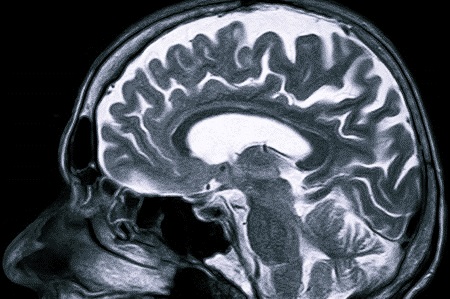

Сложна диагностика заболевания у маленьких детей. У новорожденного ребенка непросто дифференцировать симптомы, поэтому в таких случаях адекватное лечение начинается только после специфической диагностики (КТ, МРТ и т.д.).

- Магнитно-резонансная томография. С помощью МРТ достаточно быстро устанавливается точное расположение воспалительного очага в мозге человека.